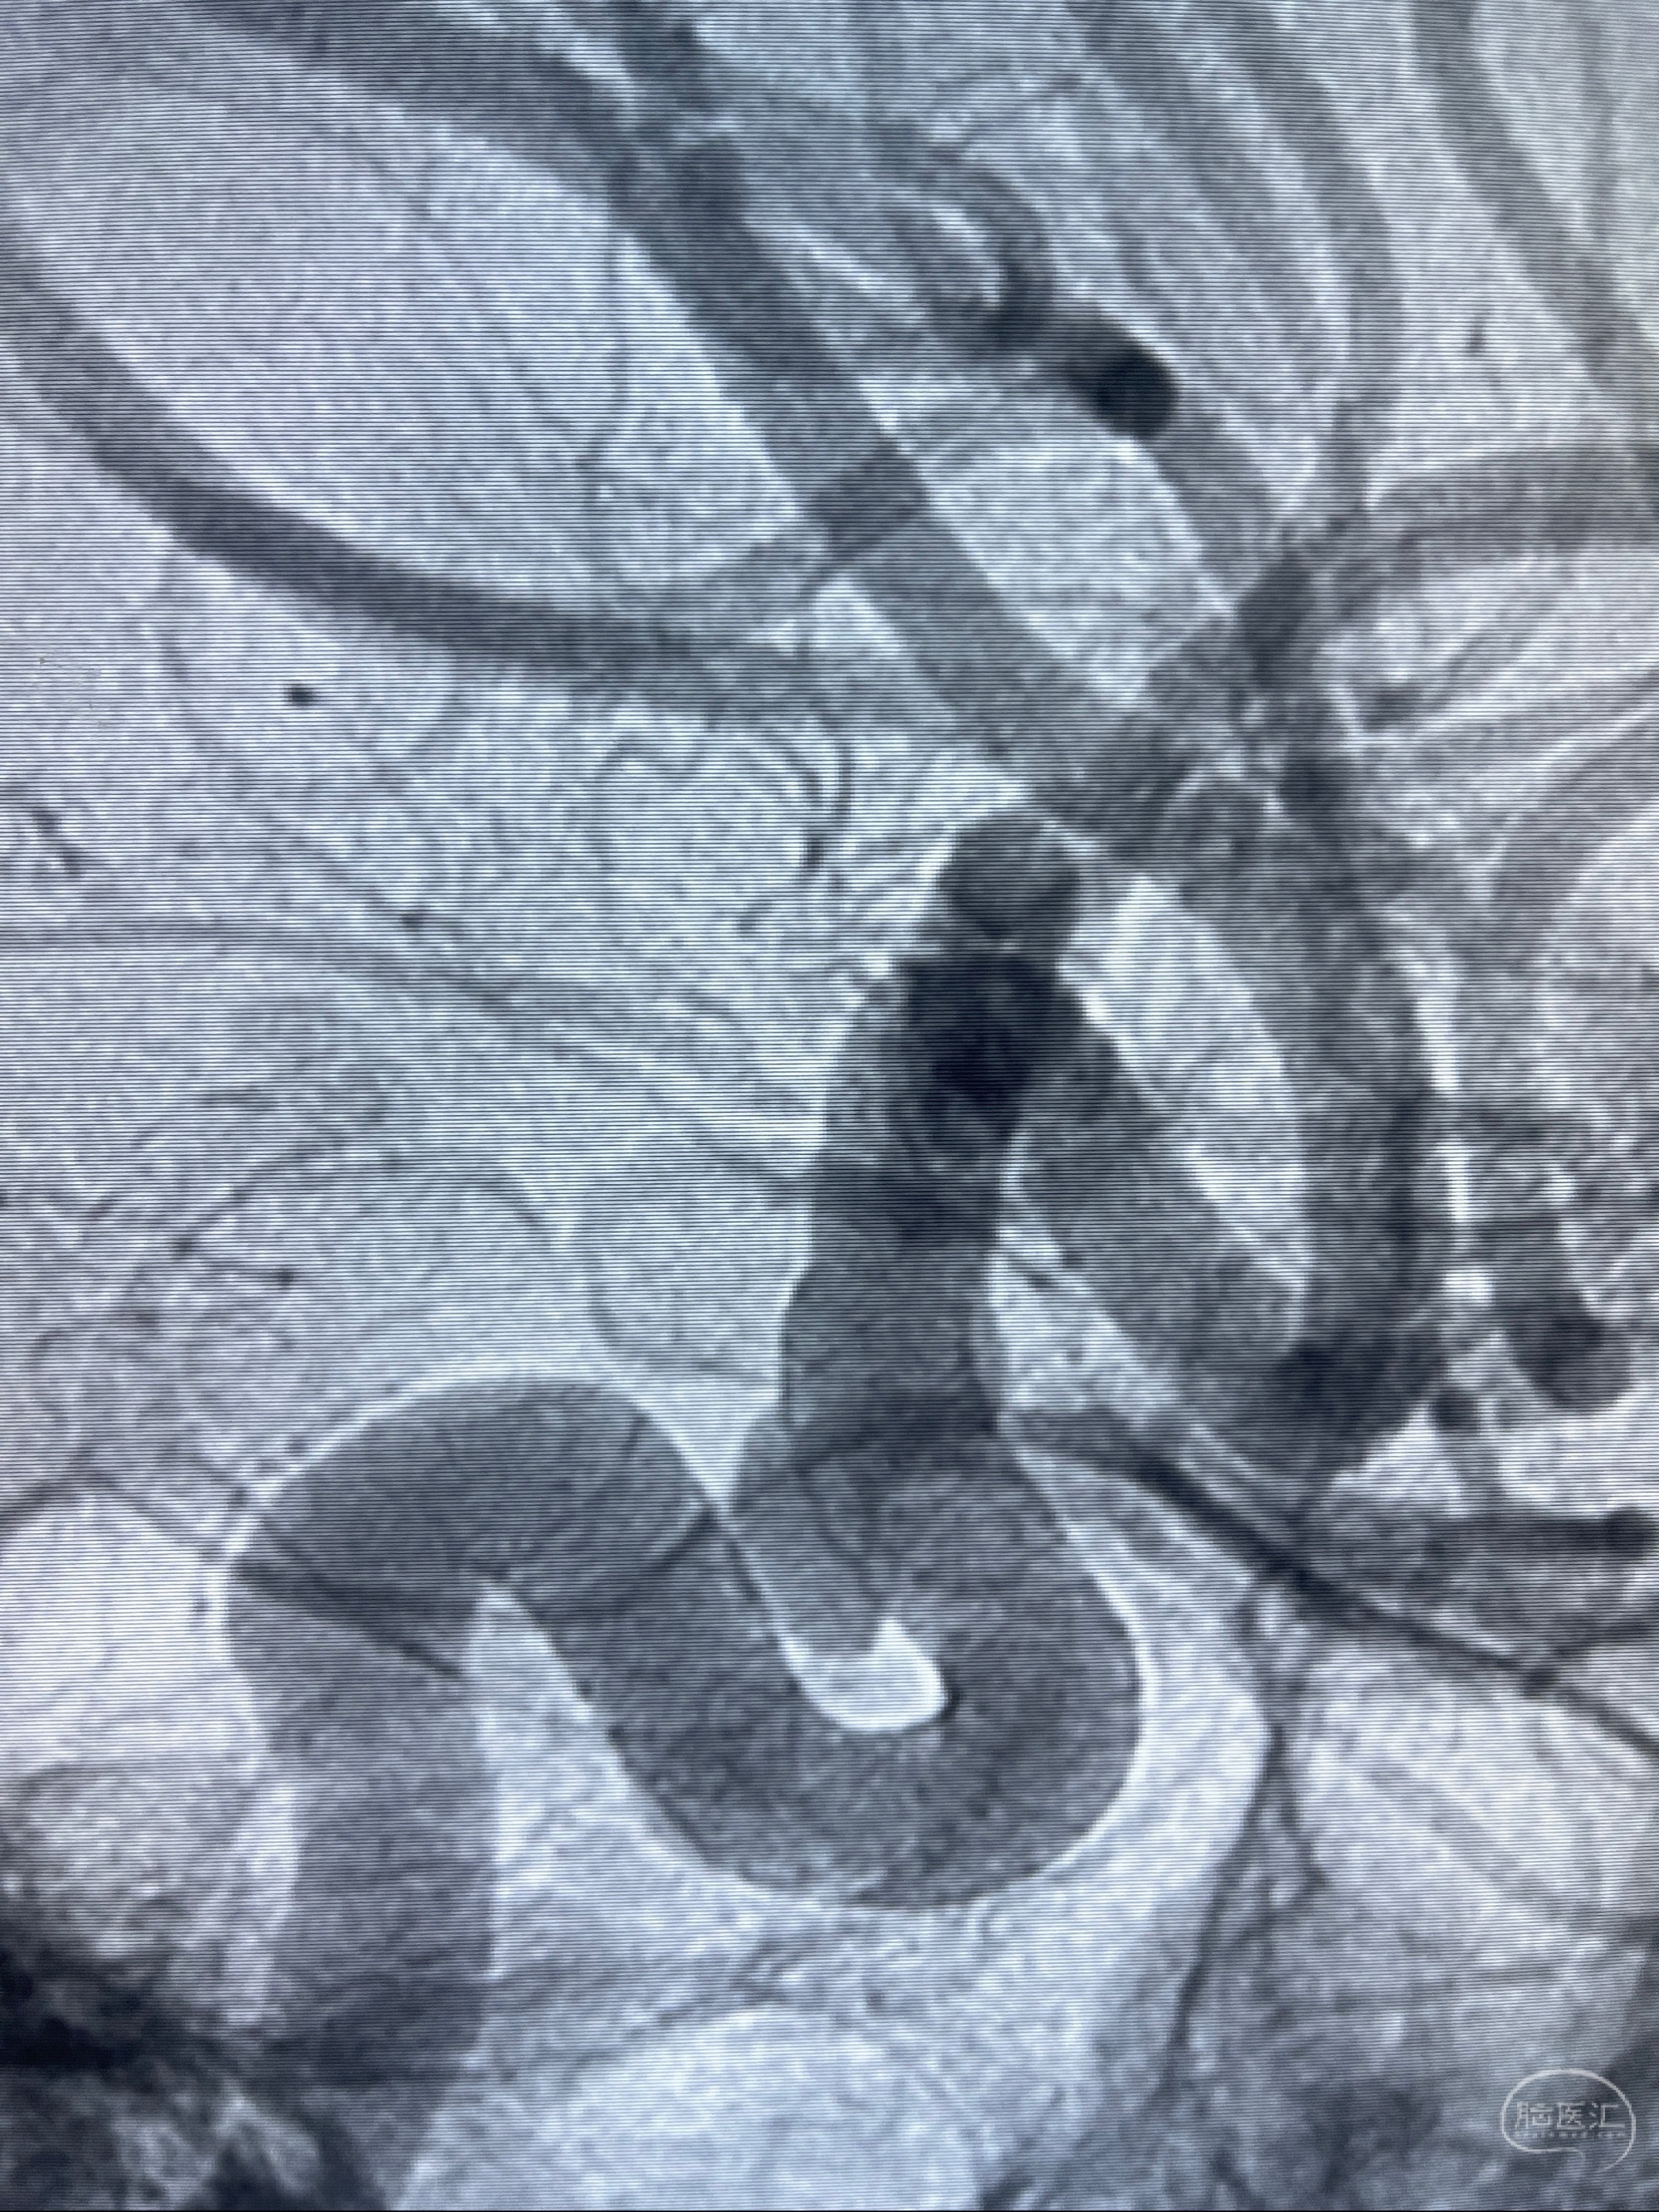

CTA示:右侧颈内动脉C6段见指向下方的突起,余左侧颈内动脉、双侧椎动脉、大脑前动脉、大脑中动脉、大脑后动脉及基底动脉走形正常,未见明显扩张及狭窄,局部未见明显瘤样扩张。

看原图,应该有两侧动脉瘤😅

2023-07-27全脑血管造影:双侧颈内动脉眼动脉段动脉瘤,右侧较大